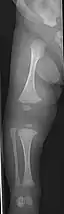

- Type V – Having the same clinical features as type IV, it can be clinically distinguished by observing a "mesh-like" appearance to a bone biopsy under a microscope. Type V can be further distinguished from other types of OI by the "V triad": an opaque band (visible on X-ray) adjacent to the growth plates; hypertrophic calluses (abnormally large masses of bony repair tissue) which form at fracture sites during the healing process; and calcification of the interosseous membrane of the forearm,[50] which may make it difficult to turn the wrist.[1]: 429 Other features of this condition may include pulled elbow, and, as in other types of OI, long bone bowing and hearing loss.[64] Cases of this type are caused by mutations in the IFITM5 gene on chromosome 11p15.5.[64][49] The separation of type V from type IV OI, its clinical type, was initially suggested even before its genetic cause was known, by Glorieux et al. in 2000.[50][65] Type V is relatively common compared to other genetically defined types of OI—4% of OI patients at the genetics department of the Brazilian Hospital de Clínicas de Porto Alegre were found to have it.[66]